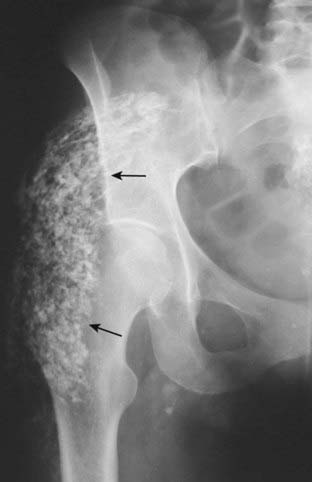

Figure 16-15 Dystrophic calcification in a calcified hematoma.

There are amorphous calcifications demonstrated in the soft tissues overlying the right hip (solid black arrows) suggesting these calcifications have formed within a solid structure. The patient had a history of prior trauma to this region. Heterotopic ossification, which would have a similar appearance, also can form in soft tissues following trauma but it usually is more organized with distinct cortices and trabeculae.